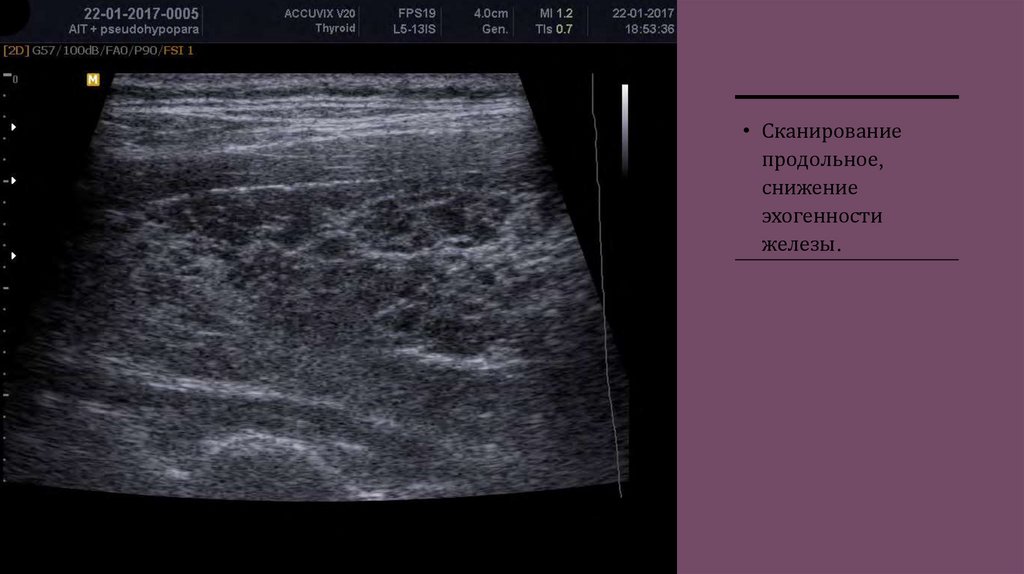

• Сканирование

продольное,

снижение

эхогенности

железы.